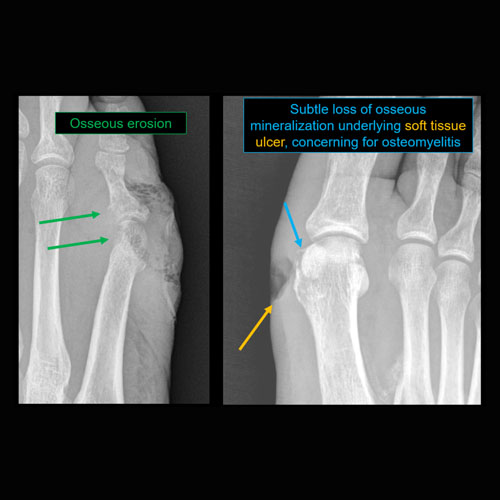

Section 1 Submit Findings CB1119 Findings Findings There are limitations. Yes No There is soft tissue reticulation, fullness, or obscuration of normal fat planes. Yes No There is soft tissue ulceration. Yes No There is soft tissue gas. Yes No There is a foreign body. Yes No There are fractures. Yes No There is periosteal reaction or osseous destruction suggesting osteomyelitis. Yes No There is cloaca, sequestrum, or involucrum. Yes No There is a joint effusion. Yes No There is periarticular osteopenia or erosions to suggest septic arthritis. Yes No There is malalignment, degenerative changes, or other gross internal derangement of the visualized joints. Yes No